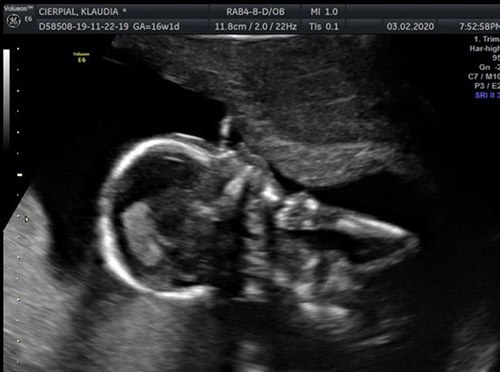

Klaudia Cierpial (18 tuổi, đến từ Scotland) đi siêu âm ở tuần thứ 20 của thai kỳ và biết được con gái của cô khỏe mạnh bình thường. 6 tuần sau đó, tức ở tuần thứ 26, Klaudia chuyển tới nhà bạn đời của mình là Brad Sheldon (21 tuổi) ở Airdrie, North Lanarkshire (Scotland) sinh sống. Khi vừa chuyển tới chưa bao lâu, Klaudia bắt đầu cảm thấy đau bụng.

Thế nhưng, khi siêu âm, kỹ thuật viên không thể tìm thấy nhịp tim của thai nhi. Sau đó, Klaudia nhận được tin sét đánh rằng con gái của cô đã qua đời trong bụng do dây rốn ngắn và xoắn nhiều vòng, làm hạn chế máu và oxy được chuyển đến nhau thai. Hai tiếng sau, bé gái Bé Maya Iwona Sheldon chào đời trong tình trạng chết lưu tím tái từ trong bụng mẹ.

Dây rốn của Maya quá ngắn và xoắn chỉ có thể phát hiện khi siêu âm. Triệu chứng này sẽ hạn chế sự phát triển của thai nhi và tăng tỷ lệ mắc bệnh ở thai nhi.